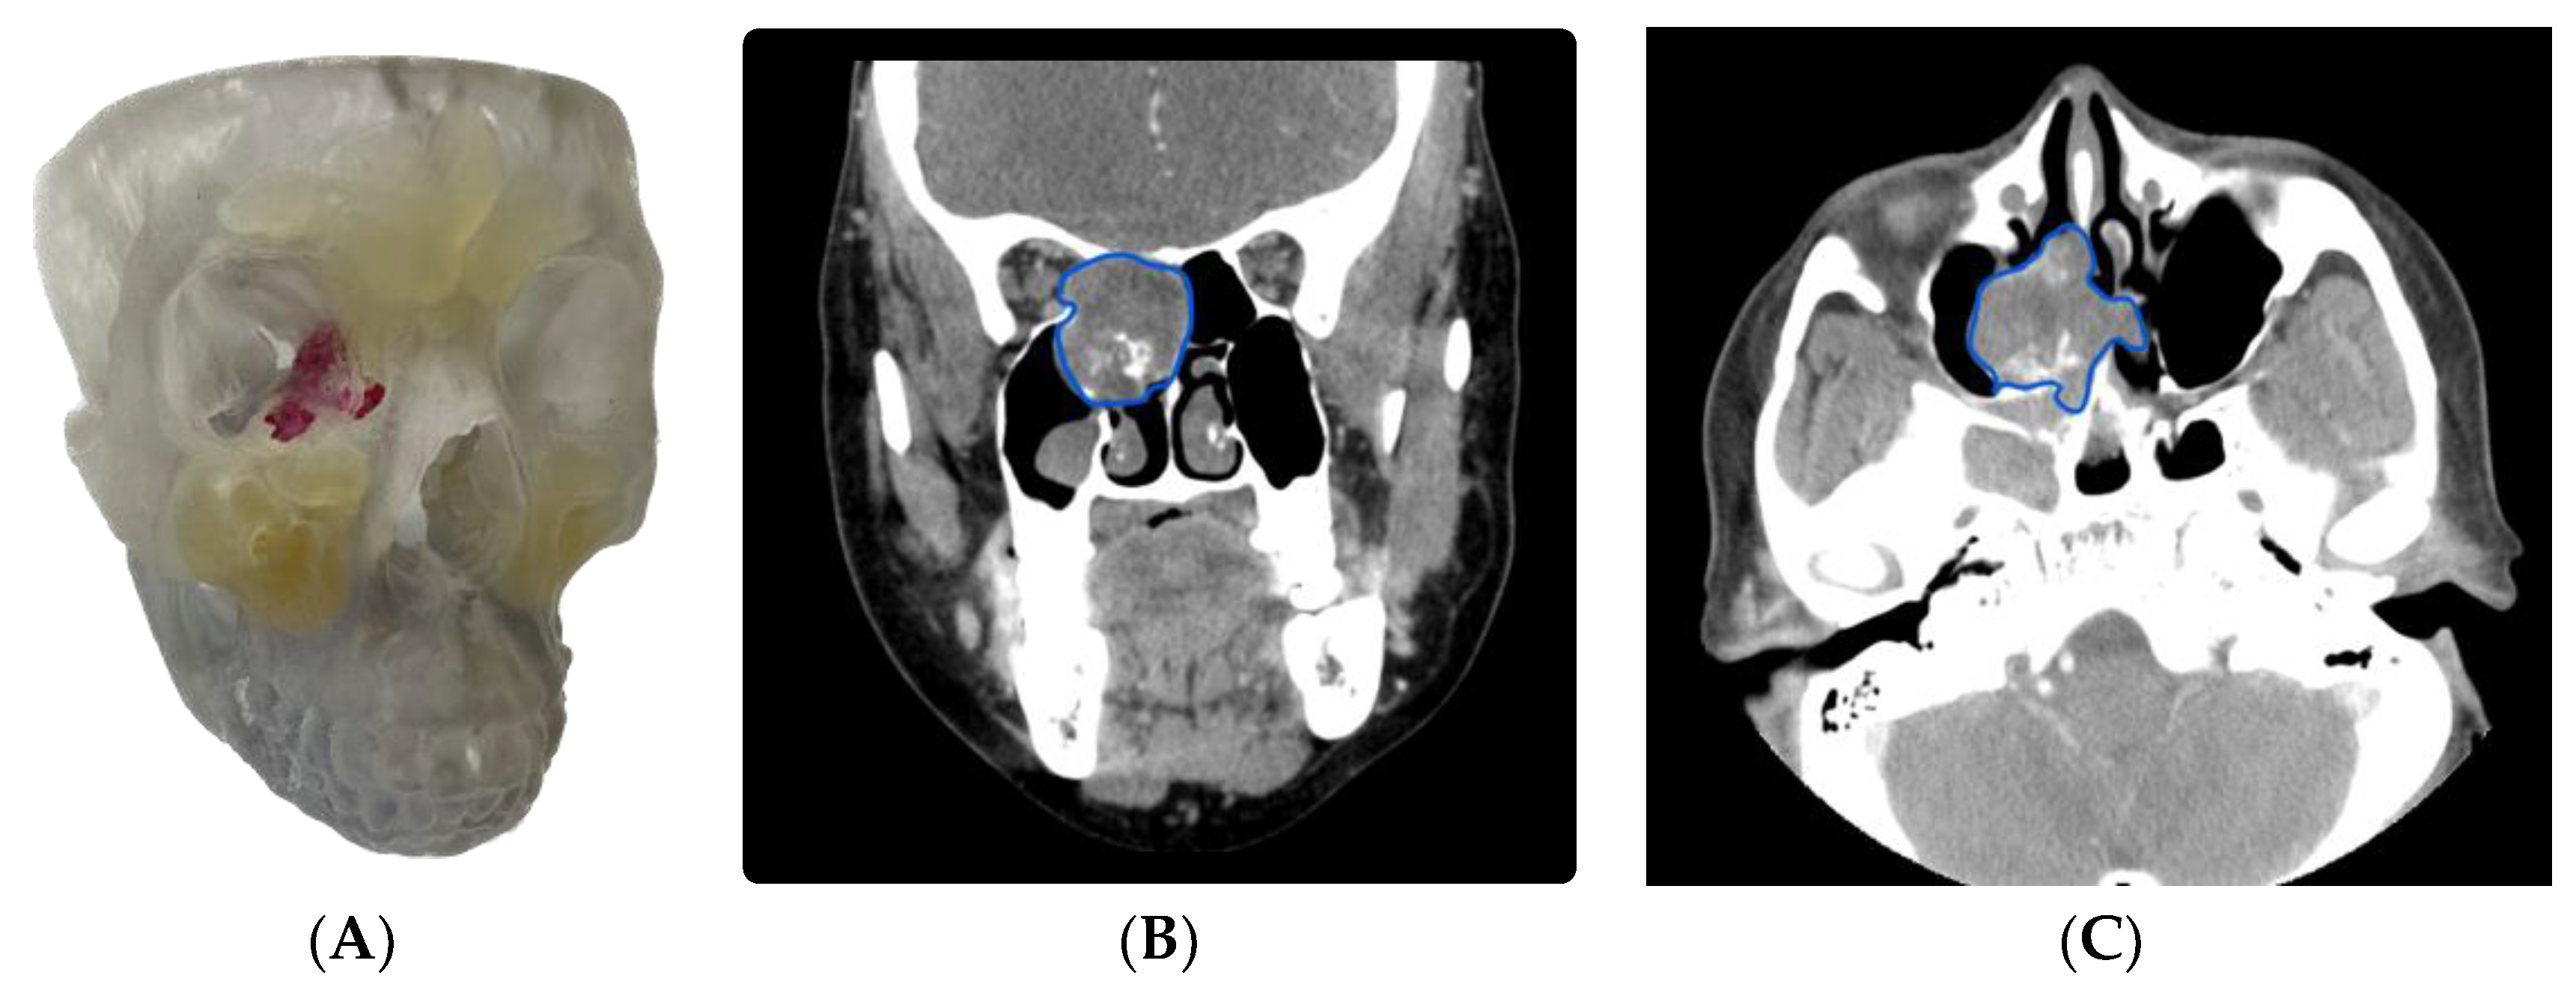

3.1.2. Case 2: Employing a 3D Model to Enhance Patient Communication